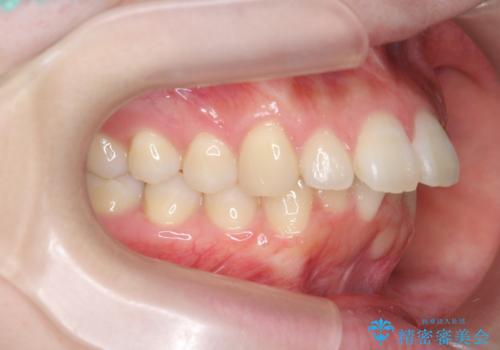

マウスピースで出っ歯感の改善

- 上の前歯が出ている感じを治したい、と矯正治療を希望され来院されました。

上顎歯列の突出感を改善すべくIPRを行い、下顎歯列を小さくすることで前歯の角度を大きく是正します、。

下顎歯列は元々前歯が1本少なく小さなアーチでしたが、下顎に合わせ上顎歯列もIPRを行い小さくすることで出っ歯感を大きく改善することが出来ました。